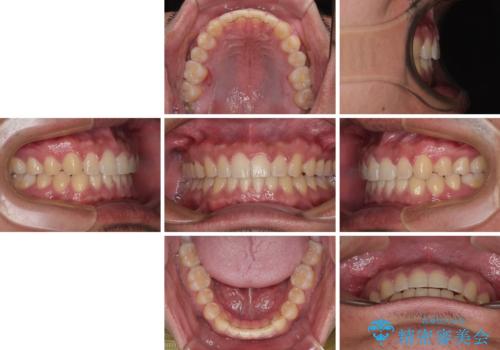

- 上下前歯の隙間を気にして来院された患者様です。

飲み込みや話をするときに舌を突出させる癖が強くあり、それが原因でスペースが空いていました。

舌のトレーニングをしっかりと行ってくださったおかげで、順調に治療を終えることができました。

舌の突出癖が速やかに改善され、後戻りによるスペースは今のところ認められておりません。